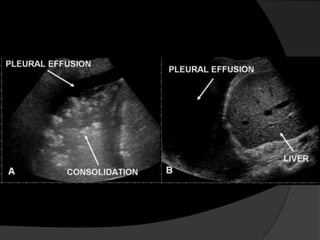

Avaliação InicialEstudos ultra-sonográficosRadiografias em decúbito lateral (Laurel)Tomografia Computadorizada (TC) para analisar o parênquima pulmonar subjacente ou mediastino.

ToracocentesePode ser realizada à beira do leito com ou sem o auxílio de ultrassonografia.A realização do procedimento guiado por ultrassonografia é indicada se houver dificuldade na obtenção de líquido pleural ou se o derrame for pequeno.Light, RW. N Engl J Med, Vol. 346, No. 25

Avaliação InicialEstudos ultra-sonográficosRadiografiasem decúbito lateral (Laurel)Tomografia Computadorizada (TC) para analisar o parênquima pulmonar subjacente ou mediastino.

ToracocentesePode ser realizadaà beira do leito com ou sem o auxílio de ultrassonografia.A realização do procedimento guiado por ultrassonografia é indicada se houver dificuldade na obtenção de líquido pleural ou se o derrame for pequeno.Light, RW. N Engl J Med, Vol. 346, No. 25